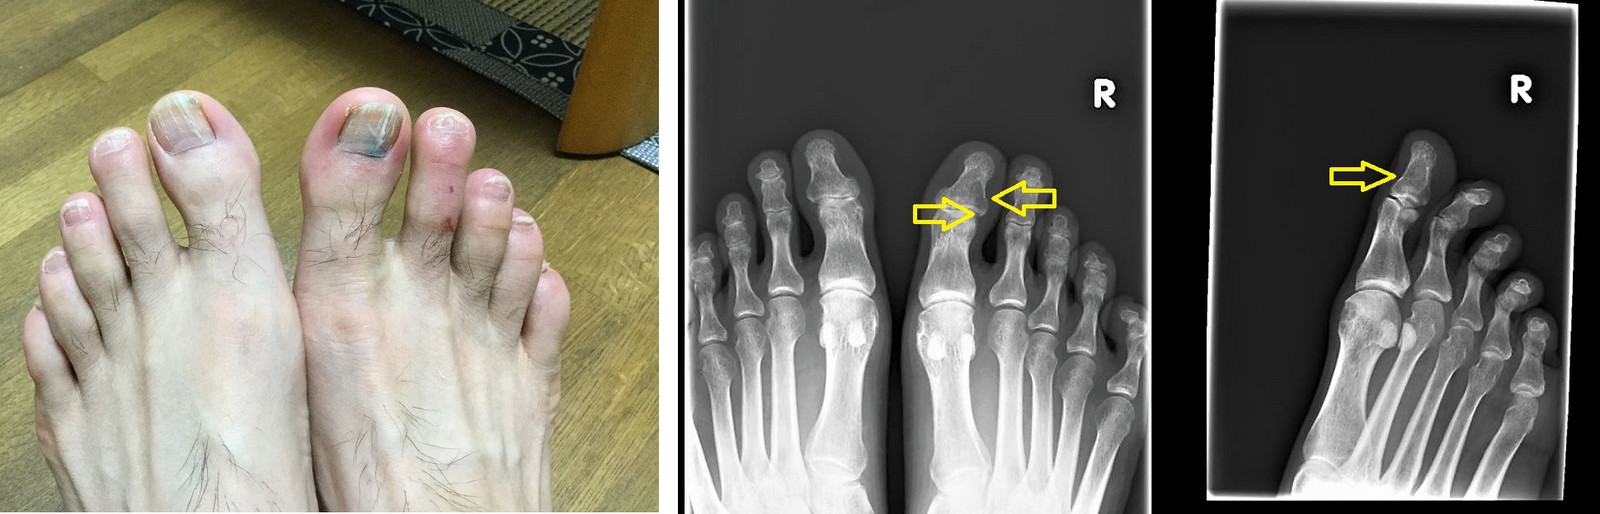

左は今回の実験におけるあっくん(当会代表)の母趾。

右は当院の患者症例で、自宅にて小趾を椅子に強打して受傷。整形で骨折の診断。当院には受傷2日後に来院(当会の一般講演会に参加したことがあり、その際に知った三上式プライトン固定を希望されて受診)。下の画像は患者症例のX線所見。

。

あっくんの母趾は受傷直後にBFIを施行し、翌日からの日常業務にほとんど支障なし。処置はスキンラップのみ(アルケア社のオルソラップを使用)。つまり固定処置が不要だったのです。